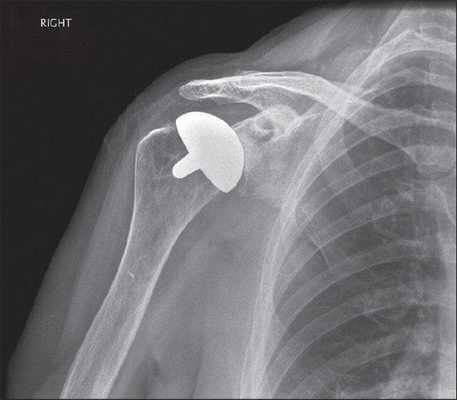

- Поверхностное. Применяется, когда минимальны повреждения головки кости пациента и много костной ткани можно сохранить. Головка обтачивается специальным инструментом, на нее «сажается» имплантат, замещающий собой поверхность сустава.

- Однополюсное. Производится имплантация либо лопаточной впадины, либо костной головки.

Для однополюсного эндопротезирования используются гемипротезы, то есть заменяющие только одну часть сустава. По способу установки делятся на поверхностные и штыревые (внедряются в кость).